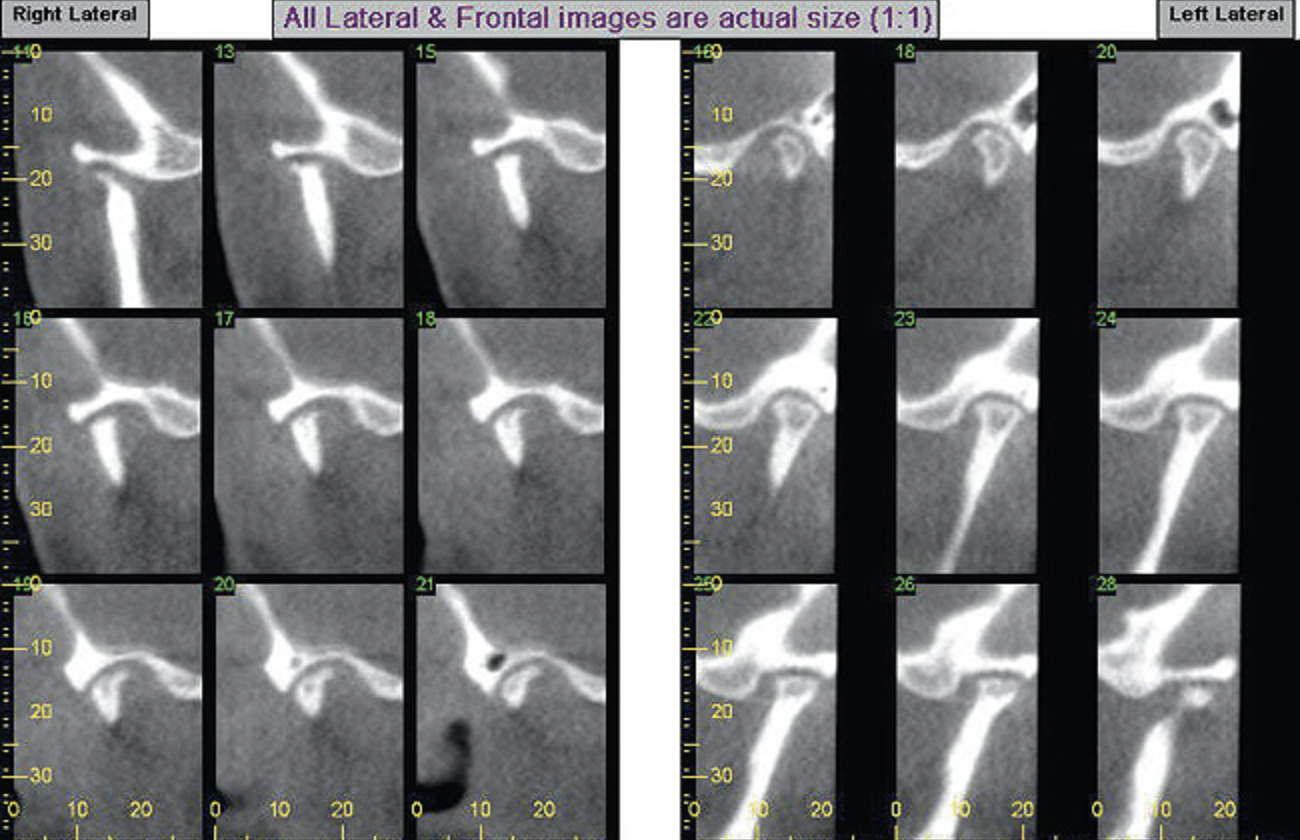

Figure 7A  This case is an example of the importance of evaluating the bite with the joints seated in a stable position. Orthodontic treatment was rendered to correct a

Figure 7A

Figure 7B  This case is an example of the importance of evaluating the bite with the joints seated in a stable position. Orthodontic treatment was rendered to correct a

Figure 7B

Figure 7C This case is an example of the importance of evaluating the bite with the joints seated in a stable position. Orthodontic treatment was rendered to correct a

Figure 7C

Figure 7D  This case is an example of the importance of evaluating the bite with the joints seated in a stable position. Orthodontic treatment was rendered to correct a

Figure 7D